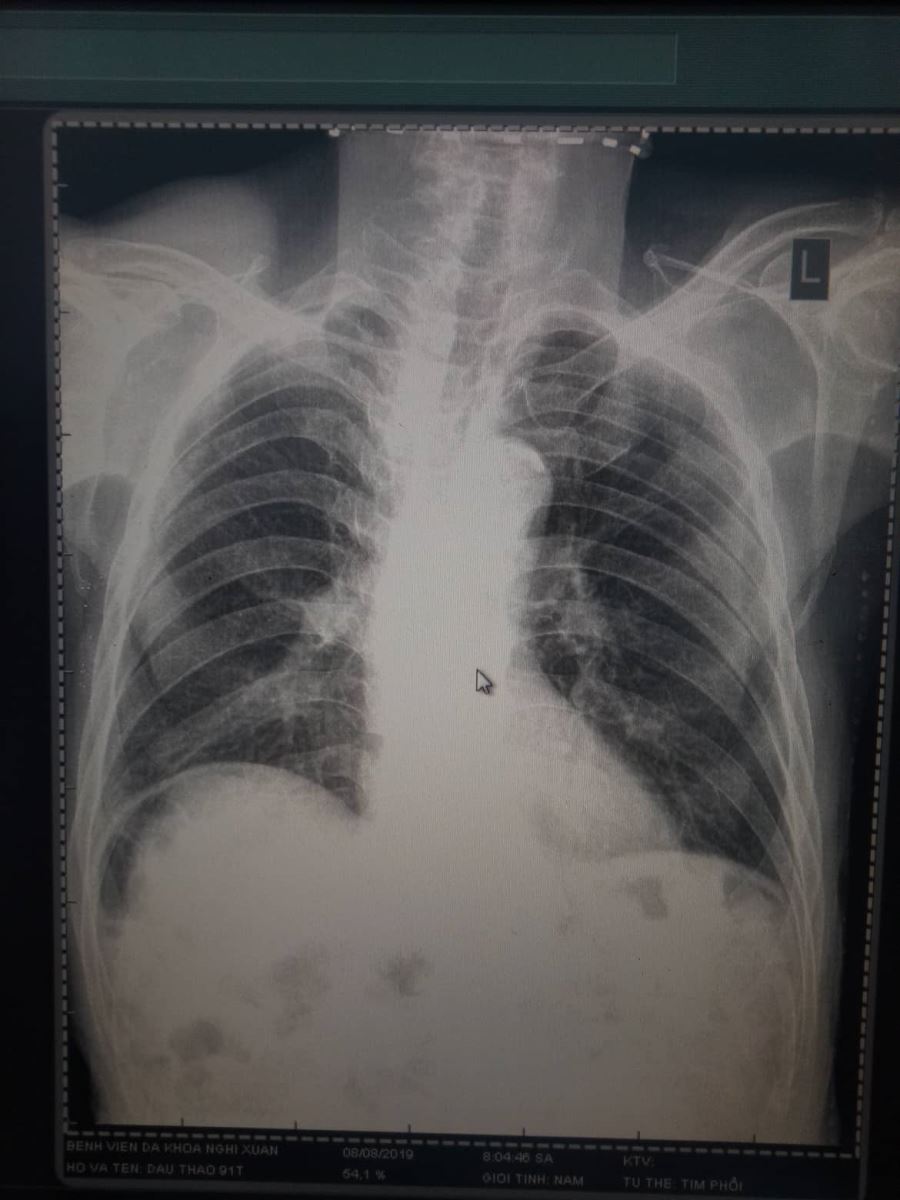

Nhân một trường hợp dấu hiệu Chilaiditi của bệnh nhân Đ.T, 91 tuổi thăm khám tại bệnh viện Đa Khoa Nghi Xuân. Dấu hiệu Chilaiditi được cho là một dấu hiệu hiếm gặp với xác xuất phát hiện qua phim chụp XQ bụng đứng là 0,1% có thể tăng lên đến 1% tùy theo độ tuổi.

Dấu hiệu Chilaiditi được đặt theo tên của bác sĩ X quang Hy Lạp Demetrius Chilaiditi, người đầu tiên mô tả, khi đang làm việc ở Vienna năm 1910. Là một tình trạng hiếm gặp, gây đau, khi một đoạn ruột già (thường là đại tràng ngang) di chuyển và bị kẹt giữa cơ hoành và gan, dấu hiệu này có thể được quan sát thấy trên phim X quang bụng đứng hoặc tim phổi thẳng.

Hinh ảnh XQuang có dấu hiệu về Chilaiditi

Bệnh nhân 91 tuổi, đến khám với triệu chứng đau tức vùng thượng vị, sau khi chụp XQ thấy hình ảnh như hình trên, xét nghiệm cho thấy công thức máu bình thường, amilaza trong giới hạn cho phép. Trên siêu âm, ghi nhận không khảo sát được gan qua mặt cắt liên sường do vướng hơi và không ghi nhận bất thường nào khác. Bệnh nhân được chẩn đoán với dấu hiệu Chilaiditi trên phim chụp XQ và nhập viện theo dõi. Sau 2 ngày, toàn trạng bệnh nhân ổn định, được tư vấn kỹ về các nguy cơ biến chứng và ra viện.